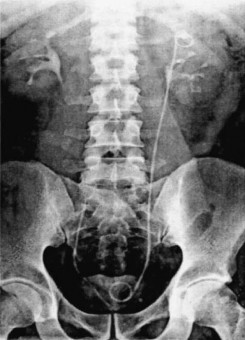

Vị trí của của đầu ống thông niệu quản liên quan đến mức độ các triệu chứng đường tiết niệu. Đầu dưới thông JJ nằm vượt quá đường giữa bàng quang (Hình 1.10) hoặc đầu trên của thông JJ nằm trong đài thận (Hình 1.11) có thể làm các triệu chứng trầm trọng thêm. Trong nghiên cứu của El-Nahas

A.R. và cs (2006) [51] ở 100 trường hợp mang ống thông niệu quản với thời gian trung bình 8 tuần (4 - 16 tuần) thì 59 trường hợp có than phiền về các triệu chứng như tiểu khó, tiểu nhiều lần, tiểu máu, tiểu gấp, đau vùng thắt lưng, đau vùng hạ vị và kết hợp ≥ 2 triệu chứng. Qua phân tích hồi quy tuyến tính đơn biến và đa biến thì các yếu tố cấy nước tiểu dương tính (RR: 19,24; KTC 95% 4,026 – 91,959; p < 0,001) đầu dưới ống thông JJ vượt đường giữa qua bên đối diện (RR: 14,572; KTC 95% 3,749 – 56,638; p < 0,001), đầu trên thông JJ nằm trong các đài thận (RR: 4,406; KTC 95% 1,068 – 18,182; p = 0,040), thời gian mang thông JJ là ảnh hưởng đến mức độ trầm trọng các triệu chứng (RR: 1,227; KTC 95% 1,004 – 1,500; p = 0,046).

Theo Rabe A. và cs (2001) [151] nghiên cứu 60 trường hợp mang ống thông niệu quản JJ trong một tuần liên quan đến than phiền về các triệu chứng của đường tiết niệu dưới. Qua phân tích kết quả nghiên cứu, các trường hợp có đầu dưới ống thông niệu quản vượt đường giữa bàng quang qua bên đối diện hoặc không cuộn tròn hết trong bàng quang (Hình 1.11) là nguyên nhân gây ra các triệu chứng đường tiểu dưới là tiểu gấp (57%), tiểu nhiều lần (47%), đau (30%), tiểu máu (25%).

Hình 1.10. Đầu dưới thông JJ vượt đường giữa bàng quang (Nguồn: El-Nahas A.R., 2006) [51] |